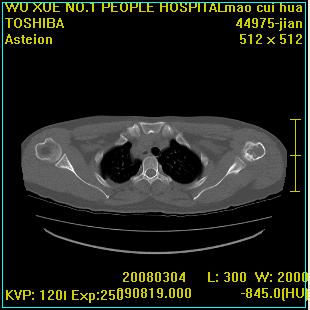

标题: CT12025:男,50岁,左肩活动受限半年。 [打印本页]

标题: CT12025:男,50岁,左肩活动受限半年。

能有x线平片就好了。肱骨头骨结构有破坏。

肩关节骨质破坏呈小囊状,其周软组织轻度肿胀,余未见异常。

考虑:肩袖损伤。建议mri。

左侧肱骨头密度不均匀,高低混杂,周围软组织略肿胀,考虑结核性病变。

考虑左侧肱骨慢性骨髓炎。

左侧肱骨头密度不均匀,高低混杂,髓腔密度稍高,周围软组织略肿胀,肌间隙模糊,考虑慢性骨髓炎可能。密切结合临床!